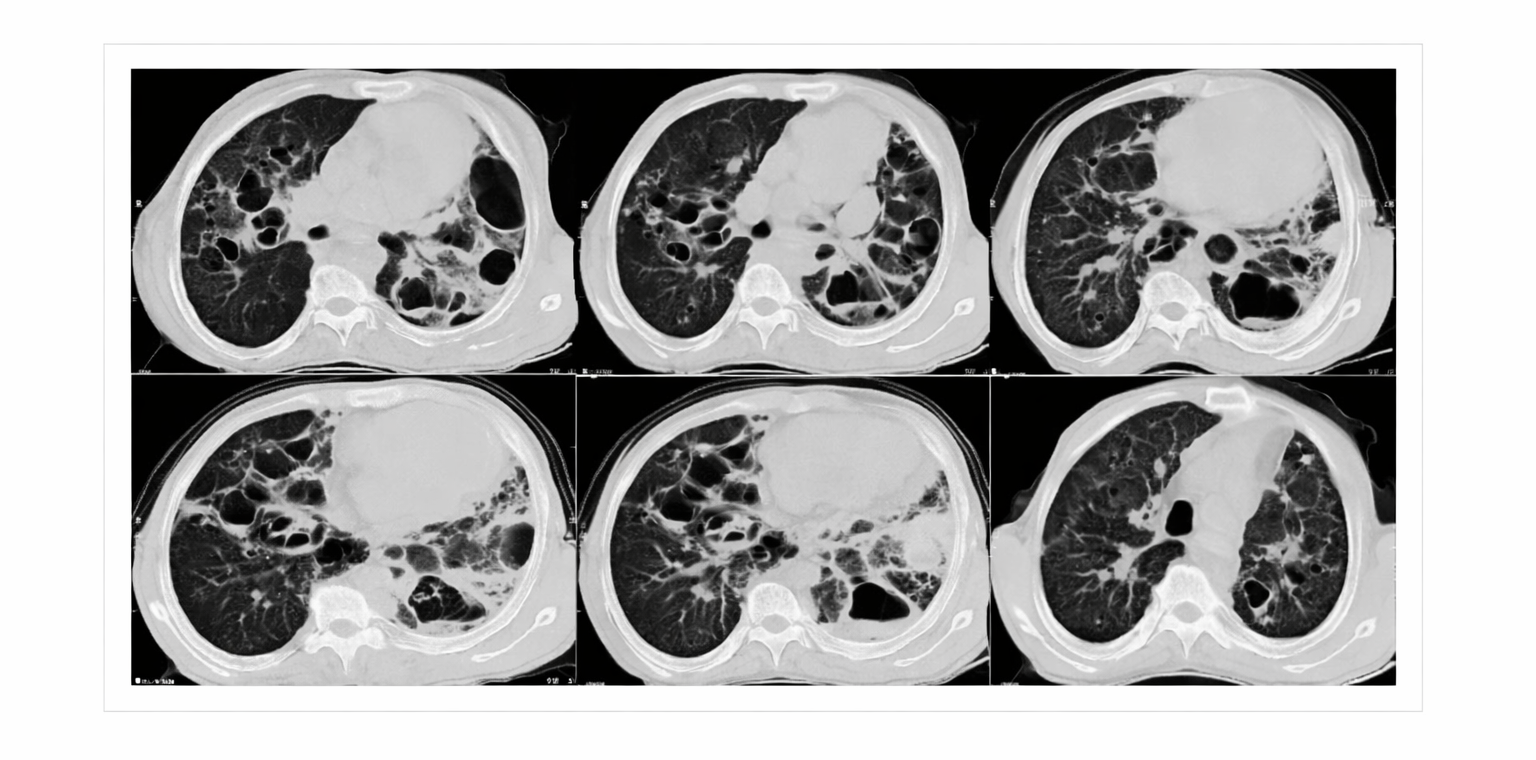

Figure 4: Chest computer tomography (CT) scan on admission showed multiple and large pneumatoceles, some with air‐fluid level consistent with superinfection mainly at middle and lower lung fields, mild consolidation, bronchiectasis, and left pleural thickening